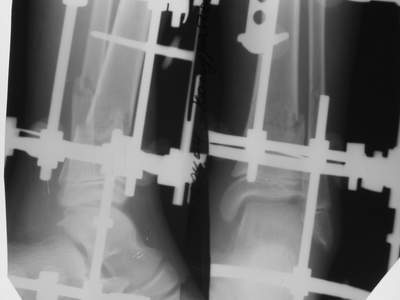

Нашел в комп-ре схожий случай:

1) з/репозиция, 2) фиксация 2 спицами, 3) аппарат, 4) фиксационные

спицы удалены...

А можно было наложить аппарат и по поводу ложного сустава...

По крайней мере не было бы укорочения (пусть и в 2 см)...